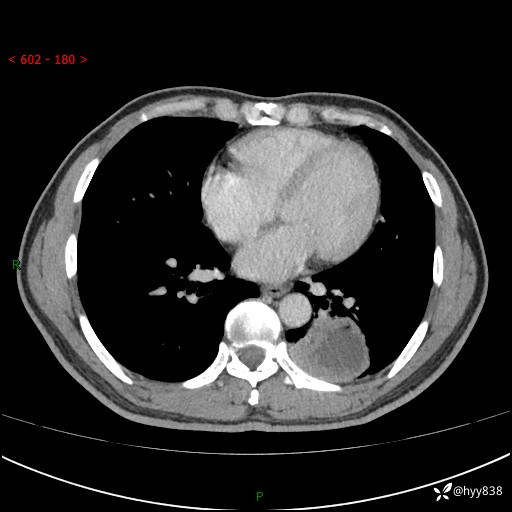

胸部CT平扫

增强

下肺占位,穿刺明确病理